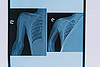

После обследования пациента было принято решение о госпитализации и проведении остеотомии, то есть удлинению сегмента при помощи спицевого аппарата. Операция по удлинению верхней трети плечевой кости продолжалась около полутора часов. Специалистами Центра травматологии было произведено рассечение плечевой кости и установка спицевого аппарата внешней фиксации для дистракции – растяжения и удлинения кости. Для образования регенерата растяжение выполнялось по 1 миллиметру в сутки. Пациент провел с аппаратом на плече 5 месяцев, за это время укорочение было компенсировано на 7,5 сантиметров.

В ноябре 2022 года на плановой госпитализации рентген-контроль показал, что плотность сформированного регенерата удовлетворительная. Пациенту был удален аппарат внешней фиксации. В настоящее время юноша чувствует себя хорошо, отмечает, что даже болевых ощущений после снятия аппарата не испытывал. Сейчас он вернулся к полноценной жизни.